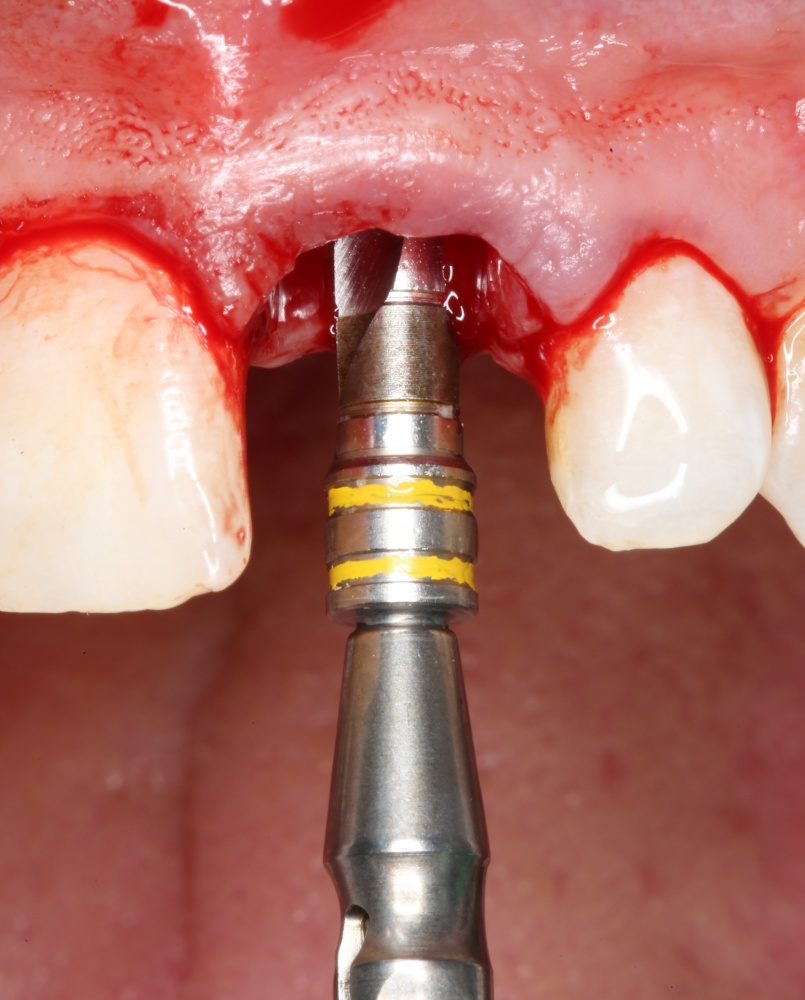

Рекомендации по установке имплантов. Для всех. Часть II.